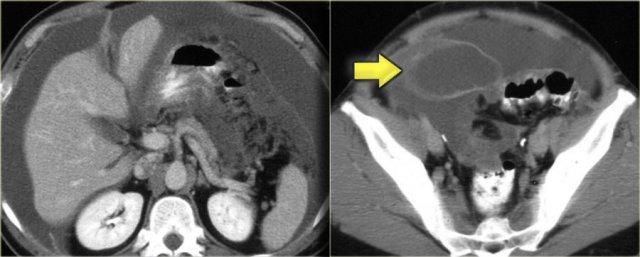

Hình bên trái là CT minh họa omental cake ở bệnh nhân ung thư buồng trứng.

Hình bên trái là bệnh nhân ung thư biểu mô phổi.

Khối đặc đơn độc này được phát hiện ở vùng chậu.

Dựa trên tiền sử bệnh, tổn thương này được nghi ngờ là di căn.

Các khối u đặc đơn độc khác như … có thể có biểu hiện tương tự.

Cần sinh thiết để xác định chẩn đoán.

Kết quả cho thấy đây là di căn của ung thư biểu mô phổi.

Hình bên trái là bệnh nhân với u carcinoid điển hình có vôi hóa trung tâm (mũi tên xanh dương).

Lưu ý hiện tượng co kéo ruột và dày thành ruột.

Có di căn gan (mũi tên vàng).